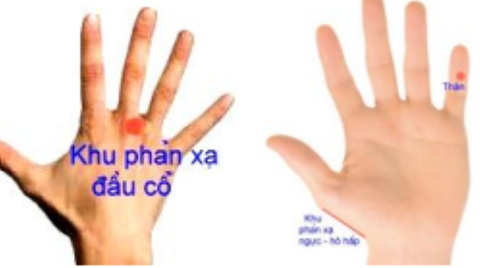

- Cách xoa bóp khu phản xạ khí quản: trước hết cần kích thích mạnh khu phản xạ hệ tiêu hóa (phối) trên bàn tay. Sau đó, xoa ấn kỹ khu phản xạ đầu, cổ và thận. Nếu có thời gian, có thể xoa bóp các ngón trên hai bàn tay thì càng tốt (xem hình).

Kích thích các khu phản xạ trên bàn tay sẽ giúp cải thiện bệnh viêm phế quản - Ảnh BSCC